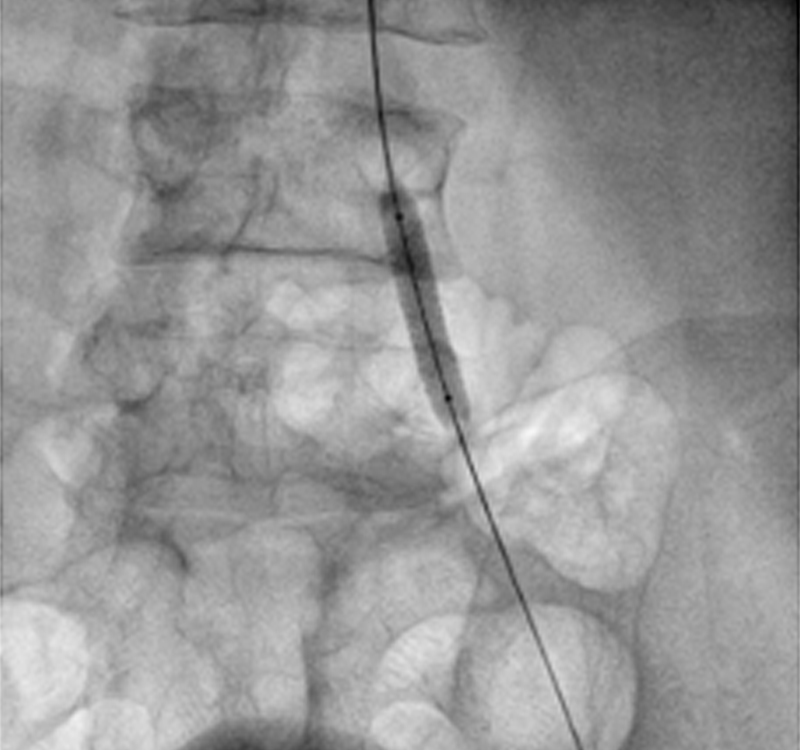

A 56 year old gentleman presented with pain in left leg while walking. He was diabetic and hypertensive. His left lower limb pulse was not palpable. Angiography of his lower limb vessel from radial route was done which showed minor plaque in right side of leg while there was significant blockage (80-90%) in the main vessel of the left leg.

Most of the cardiologist will open the critical blockage in the left leg by inserting catheter from the right leg. Doing these types of cases from radial artery (vessel of hand) is always challenging and one has to have clear idea of approach and familiarity with the hard wire used for performing these types of procedure without any complication.

Critical blockage of left leg was successfully dilated with the balloon and subsequently stent was placed without any complication. Cannula from the arm was immediately removed after the procedure and patient could walk immediately after the procedure. If we do such types of cases by femoral route, patient has to be one bed at least for next 10-12 hours and patient even not allowed to fold the legs for at least 10-12 hours. Patient was discharged successfully next day morning.